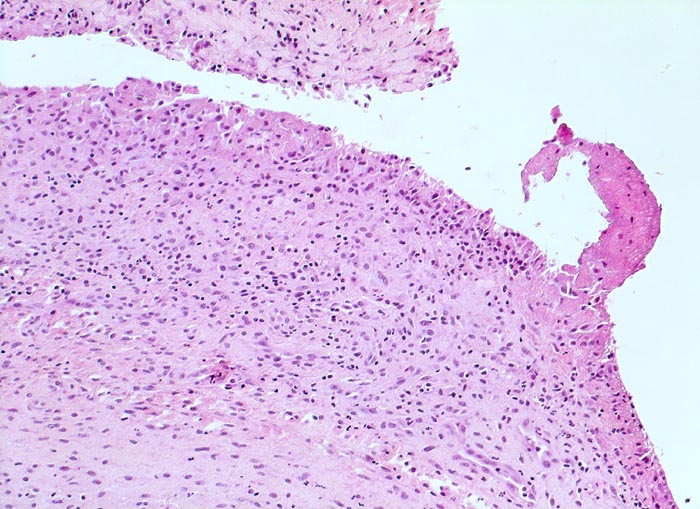

Synovialitis bei chronischer Polyarthritis

Synovialis

Verdickte synoviale Deckzellschicht. Lockeres gemischtes Entzündungsinfiltrat im Stroma. Fokale Fibrinauflagerungen.

Bekannte seropositive chronische Polyarthritis.

Histologie

100